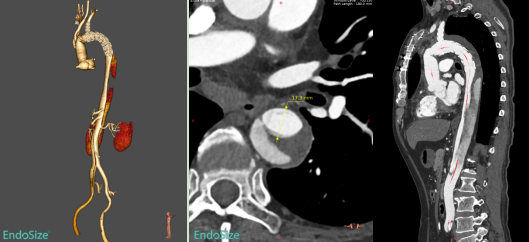

本次入组患者为60岁男性,1个多月前因急性Stanford A型主动脉夹层在我院接受“主动脉瓣交界悬吊+升主动脉及全弓置换+降主动脉象鼻支架置入+三尖瓣成形术”。术后1个月复查CTA提示:象鼻支架以远残余夹层,且夹层累及胸降主动脉、腹主动脉、右侧髂总及髂外动脉,真腔狭窄,假腔大,胸腹主动脉多发夹层破口,胸段肋间动脉以假腔供血为主。

术前CTA